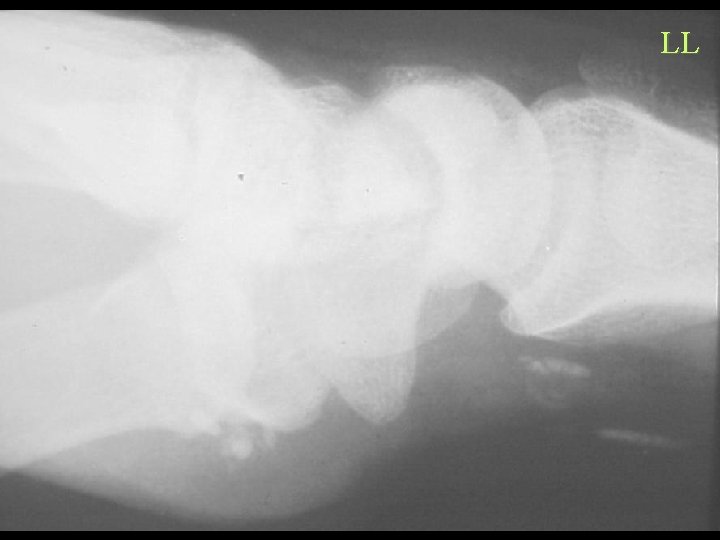

Calcification By Shape Linear and Curvilinear • Arterial – Atheroma, Aneurysm, Diabetes, HPT, Progeria, Werner’s • Nerve – Leprosy, Neurofibromatosis • Tendon and Ligament – Tendinitis, AS, Ochronosis, Fluorosis, Diabetes • Injection – Bismuth, Arsenic, Quinidine • Parasite – Cysticercosis, Guinea worm, Loa, Armillifer armillatus

LL